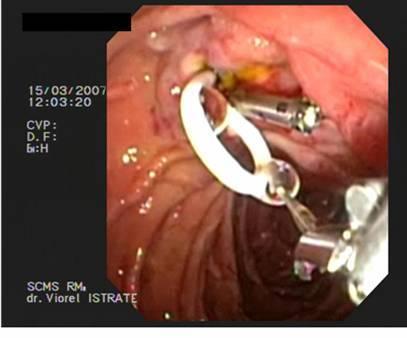

12 patients were selected (F:M, 5:7, age range 37 - 68 years) with ampullary adenoma, treated by endoscopic papillectomy. Biliary sphincterotomy was performed in 6 cases; and pancreatic sphincterotomy was performed in 3 cases. Biliary stenting was performed in 2 cases; pancreatic stent was placed in 11 cases.

En bloc resection was performed in 8 cases, and piecemeal resection in 4 cases. Complete resection R0 was noted in 10 cases. Pathology examination has show: tubulo-villous adenoma (5 patients); villous adenoma (4 patients), tubular adenoma (2 cases), adenocarcinoma (one case). Complications were immediate: bleeding (2 cases) and pancreatitis (1 case). Follow-up endoscopy reveals no ductal stenosis or recurrence.